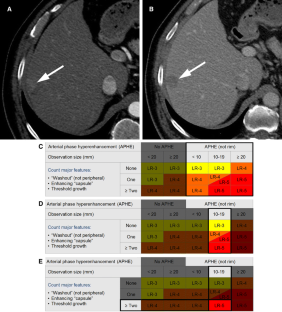

LI-RADS® algorithm: CT and MRI

The Liver Imaging Reporting and Data System (LI-RADS®) is an imaging-based diagnostic system applicable in patients at high risk of hepatocellular carcinoma (HCC). In LI-RADS, each liver observation is assigned a category that reflects probability of benignity, HCC, or other malignancy. Familiarity with the LI-RADS diagnostic algorithm is necessary to appropriately implement LI-RADS in clinical practice. This review discusses steps necessary for application of the LI-RADS algorithm and provides examples illustrating each step.